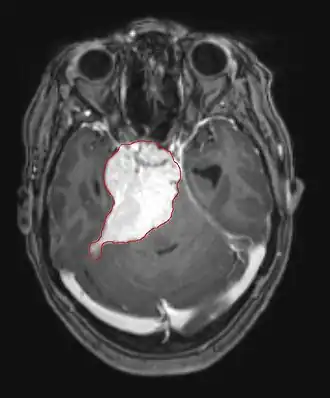

Hersenmetastasen

Hersenmetastasen zijn de meest voorkomende intracraniële neoplasmata bij volwassenen en komen tien keer vaker voor dan primaire hersentumoren. Ze stappen op 20 tot 40 procent van de volwassenen met kanker en worden voornamelijk geassocieerd met long- en borstkanker en melanoom. Deze laesies zijn het gevolg van de verspreiding van kankercellen door de bloedbaan en komen meestal voor op de kruising van grijze en witte stof, waar de dwarsdoorsnede van bloedvaten verandert, waardoor tumorcelembolie wordt opgesloten . 80 procent van de laesies komt voor in de hersenhelften, procent in het cerebellum en 5 procent in de hersenstam. Ongeveer 80 procent van de patiënten heeft een voorgeschiedenis van systemische kanker en 70 procent heeft meerdere hersenmetastasen.

Hersenmetastasen zijn de meest voorkomende intracraniële neoplasmata bij volwassenen en komen tien keer vaker voor dan primaire hersentumoren. Ze stappen op 20 tot 40 procent van de volwassenen met kanker en worden voornamelijk geassocieerd met long-en borstkanker en melanoom. Deze laesies zijn het gevolg van de verspreiding van kankercellen door de bloedbaan en komen meestal voor op de kruising van grijze en witte stof, waar de dwarsdoorsnede van bloedvaten verandert, waardoor tumorcelembolie wordt opgesloten. 80 procent van de laesies komt voor in de hersenhelften, procent in het cerebellum en 5 procent in de hersenstam. Ongeveer 80 procent van de patiënten heeft een voorgeschiedenis van systemische kanker en 70 procent heeft meerdere hersenmetastasen.

De literatuur laat gelijkwaardige resultaten zien voor chirurgie en radiochirurgie. Dit laatste lijkt handiger, effectiever en veiliger voor kleine laesies of in gebieden die niet toegankelijk zijn voor chirurgie. Radiochirurgie is een verstandig alternatief voor patiënten die om medische redenen niet geopereerd kunnen worden. Chirurgie is echter duidelijk de optimale methode om weefsels te verkrijgen voor diagnose en om de laesies te verwijderen die een massa-effect veroorzaken. Daarom moeten radiochirurgie en chirurgie beter worden beschouwd als twee complementaire maar verschillende methoden die moeten worden toegepast, afhankelijk van de verschillende situatie van de patiënt. Voor bijna 50 procent van de patiënten met een of twee hersenmetastasen komt niet in aanmerking voor chirurgische verwijdering vanwege de ontoegankelijkheid van de laesies, de omvang van de systemische ziekte of andere factoren. Deze en andere patiënten met meerdere metastasen krijgen gewoonlijk panencefale bestralingstherapie als standaardbehandeling. Bereik eigenlijk tot bijna 50 procent van hen met deze therapie een verbetering van neurologische symptomen en 50 tot 70 procent een merkbare reactie. Chemotherapie wordt zelden primair gebruikt voor hersenmetastasen.

Voor de meeste patiënten met hersenmetastasen is de mediane overleving slechts vier tot zes maanden na panencefale bestralingstherapie. Patiënten jonger dan 60 jaar met discrete laesies en gecontroleerde systemische ziekte kunnen echter een langere overleving bereiken omdat ze een agressievere behandelingsbenadering kunnen verdragen.